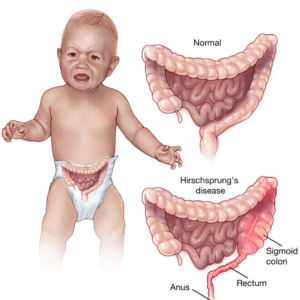

Hirschsprung’s disease